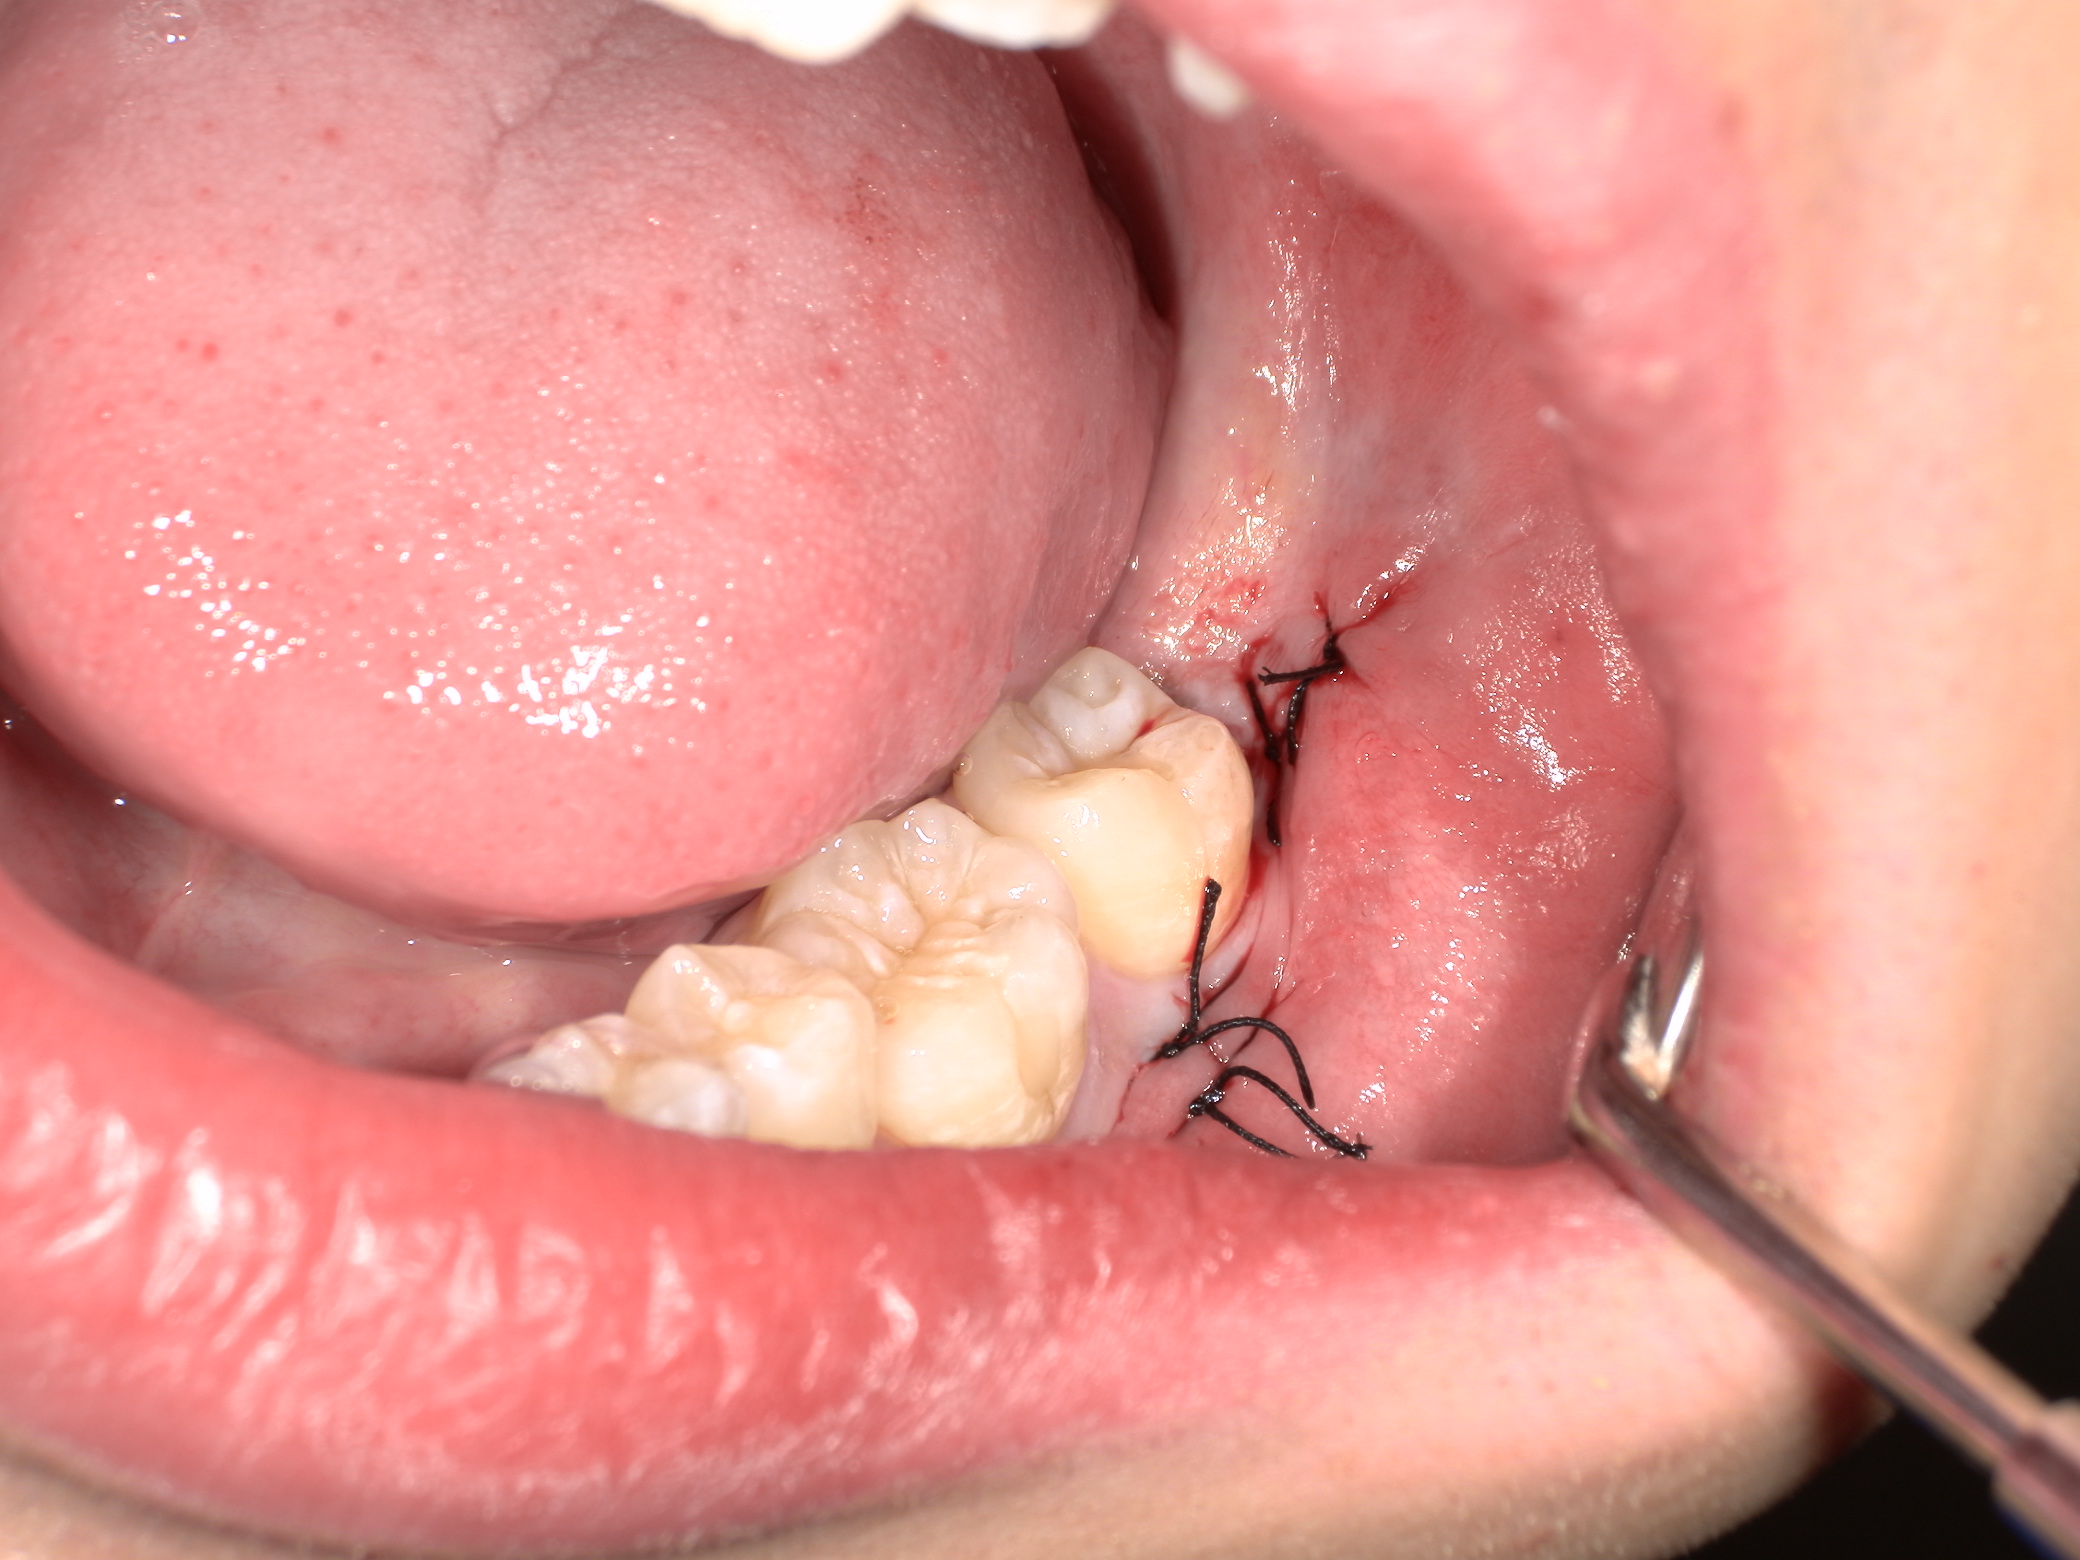

今回のケースのように歯茎を切開したり、骨を削る必要がある場合は腫れることになります。

これに関しては腫れても軽微にすることが可能です。

それはなるべく切開や骨を削ることを最小限に努め、処置時間を短くすることです。

当クリニックではCTも完備していますので、親知らずの位置や状態を事前に詳細に把握することで達成し得ることができます。